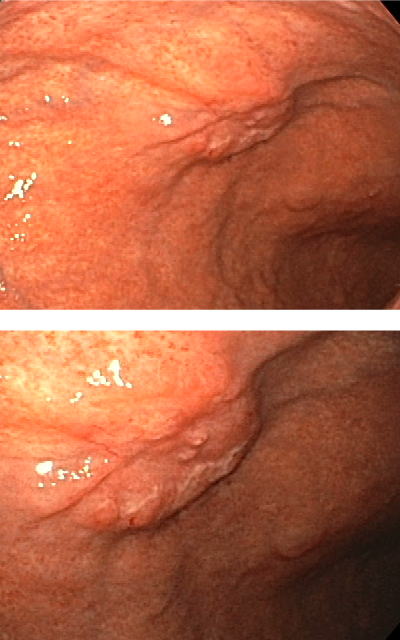

| ˆف’×ل‡(–ٍچـگ«)پ@’ء’ةچـ‚ة‚و‚é‚à‚ج | |

| ˆف’×ل‡(–ٍچـگ«)پ@چRٹàچـ‚ة‚و‚é‚à‚ج | |